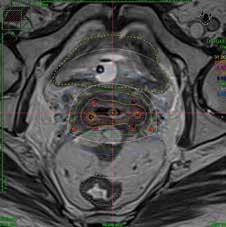

Gjennom hele prosedyren har pasienten en spinalbedøvelse og får det som kalles lett sedasjon av anestesi under overvåking. Når utstyret settes inn i pasienten, kontrolleres plasseringen med ultralyd. Det er her mulig for oss å se om utstyret vi bruker, sitter korrekt før vi tar pasienten med til MR. Vi bruker primært MR-bilder til vår doseplanlegging, der vi har to faste MR-timer hver dag. CT-bilder brukes også i noen tilfeller. Det kan også planlegges med CT-bilder. Nedenfor er prosedyren nevnt i korte trekk:

På ultralydbildet til venstre har vi aksial visning av cervix hvor utstyret er plassert. Det er brukt en rektal probe. Man kan se at i sentrum vises sonden som lys, noe som indikerer at utstyret er plassert korrekt i cervix-kanalen. Det samme med nålene som lyser opp på sidene. Til høyre vises utstyret ferdig rekonstruert og optimalisert ved bruk av MR-bilder. Også vist i aksial visning.